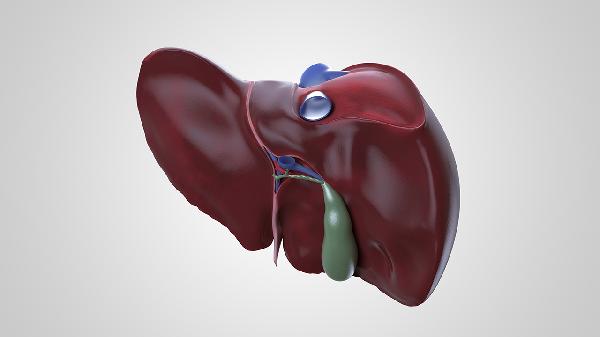

肝脏不好的表现症状主要有皮肤黄染、消化异常、全身乏力、肝区不适、出血倾向等。肝脏是人体重要的代谢器官,其功能受损时可能出现多种症状,症状的严重程度与肝脏损伤程度相关。